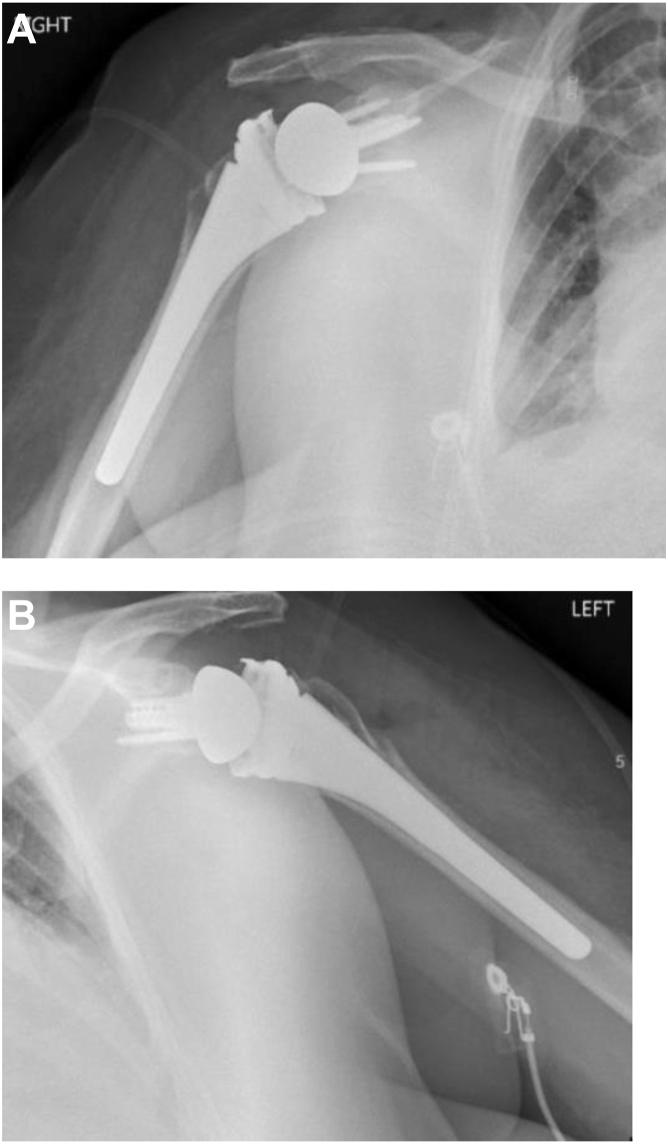

Single-stage bilateral uncemented reverse shoulder arthroplasty for traumatic proximal humerus fractures: a case report.

JSES Rev Rep Tech. 2024 May 6;4(3):504-510. doi: 10.1016/j.xrrt.2024.04.009. eCollection 2024 Aug.